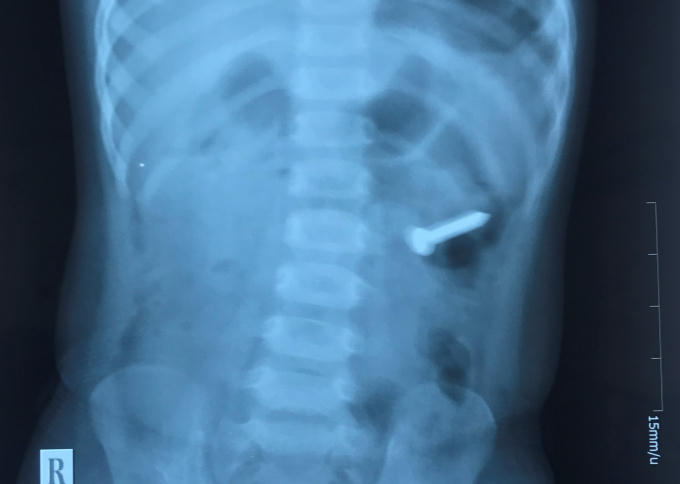

Theo gia đình cho biết, cháu chơi một chiếc đinh ốc xoắn và vô tình nuốt phải đinh qua thăm khám và chụp Xquang các Bác sĩ phát hiện 1 dị vật cản quang trong dạ dày. Bệnh viện đã tiến hành hội chẩn và quyết định tiến hành nội soi gây mê để lấy dị vật ra.

“Sau khi đặt máy xác định dị vật xuống sâu hơn ở D3 tá tràng so với phim X – Quang. Do dị vật có bề mặt xoắn ốc lại dài 3cm so với kích thước lồng ruột của trẻ 2 tuổi nên thủ thuật tiến hành rất khó khăn.